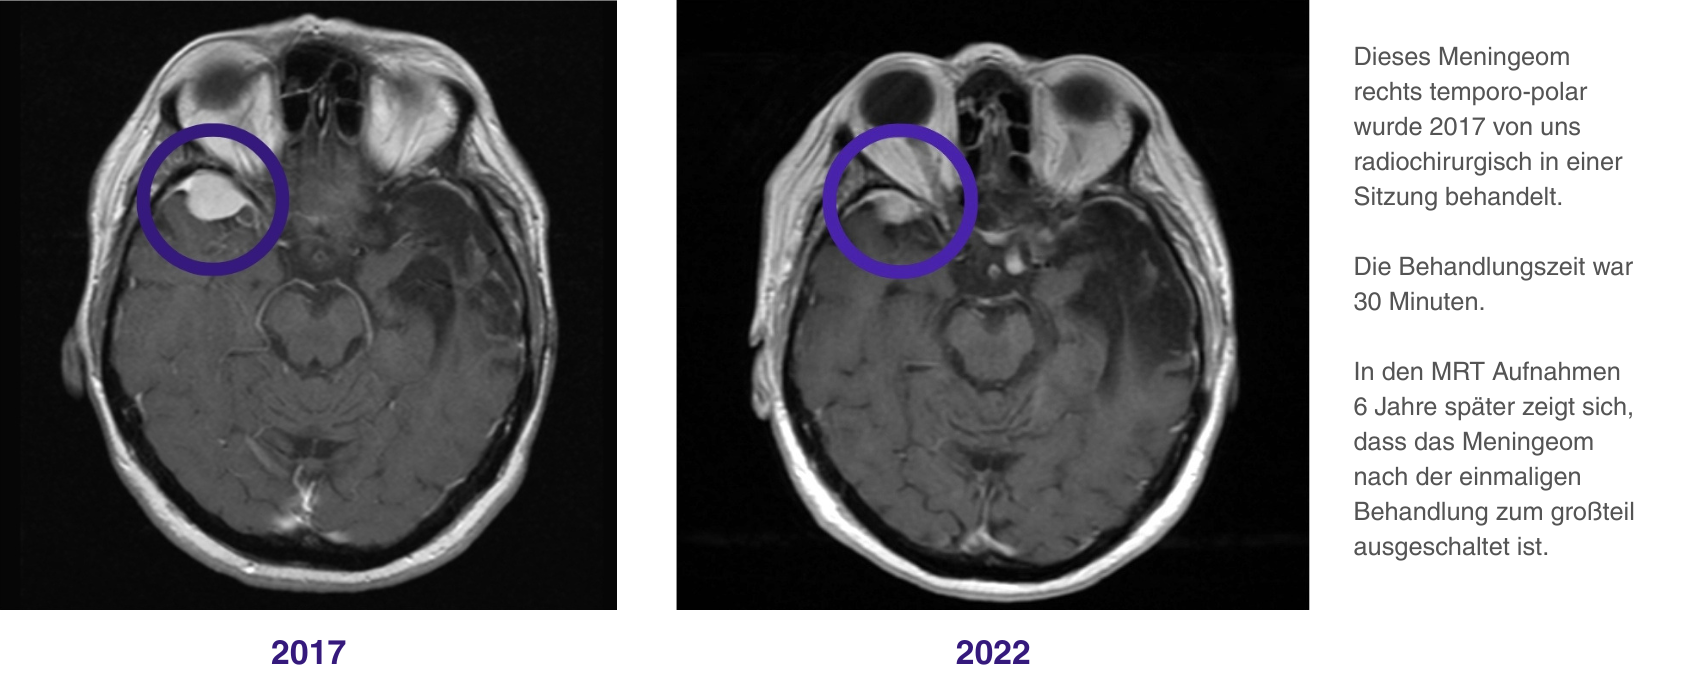

Die robotergeführte, hochpräzise Behandlung mit dem CyberKnife oder ZAP-X, wie wir sie hier im ERCM durchführen, kann als primäre Therapieform bei kleineren, schwer operativ zu entfernenden Tumoren (z. B. Sinus Cavernosus Meningeom) sehr gut eingesetzt werden [3]. In den meisten Fällen sprechen wir von einer einzigen Behandlungssitzung, durch die eine hohe Tumorkontrolle erreicht werden kann. Das heißt, ein erneutes Tumorwachstum wird im Idealfall verhindert.

Im ERCM verfügen wir über umfassende radiochirurgische Erfahrung beim Meningeom. Oft erreichen wir mit einer einzigen Therapiesitzung eine hohe Tumorkontrolle.